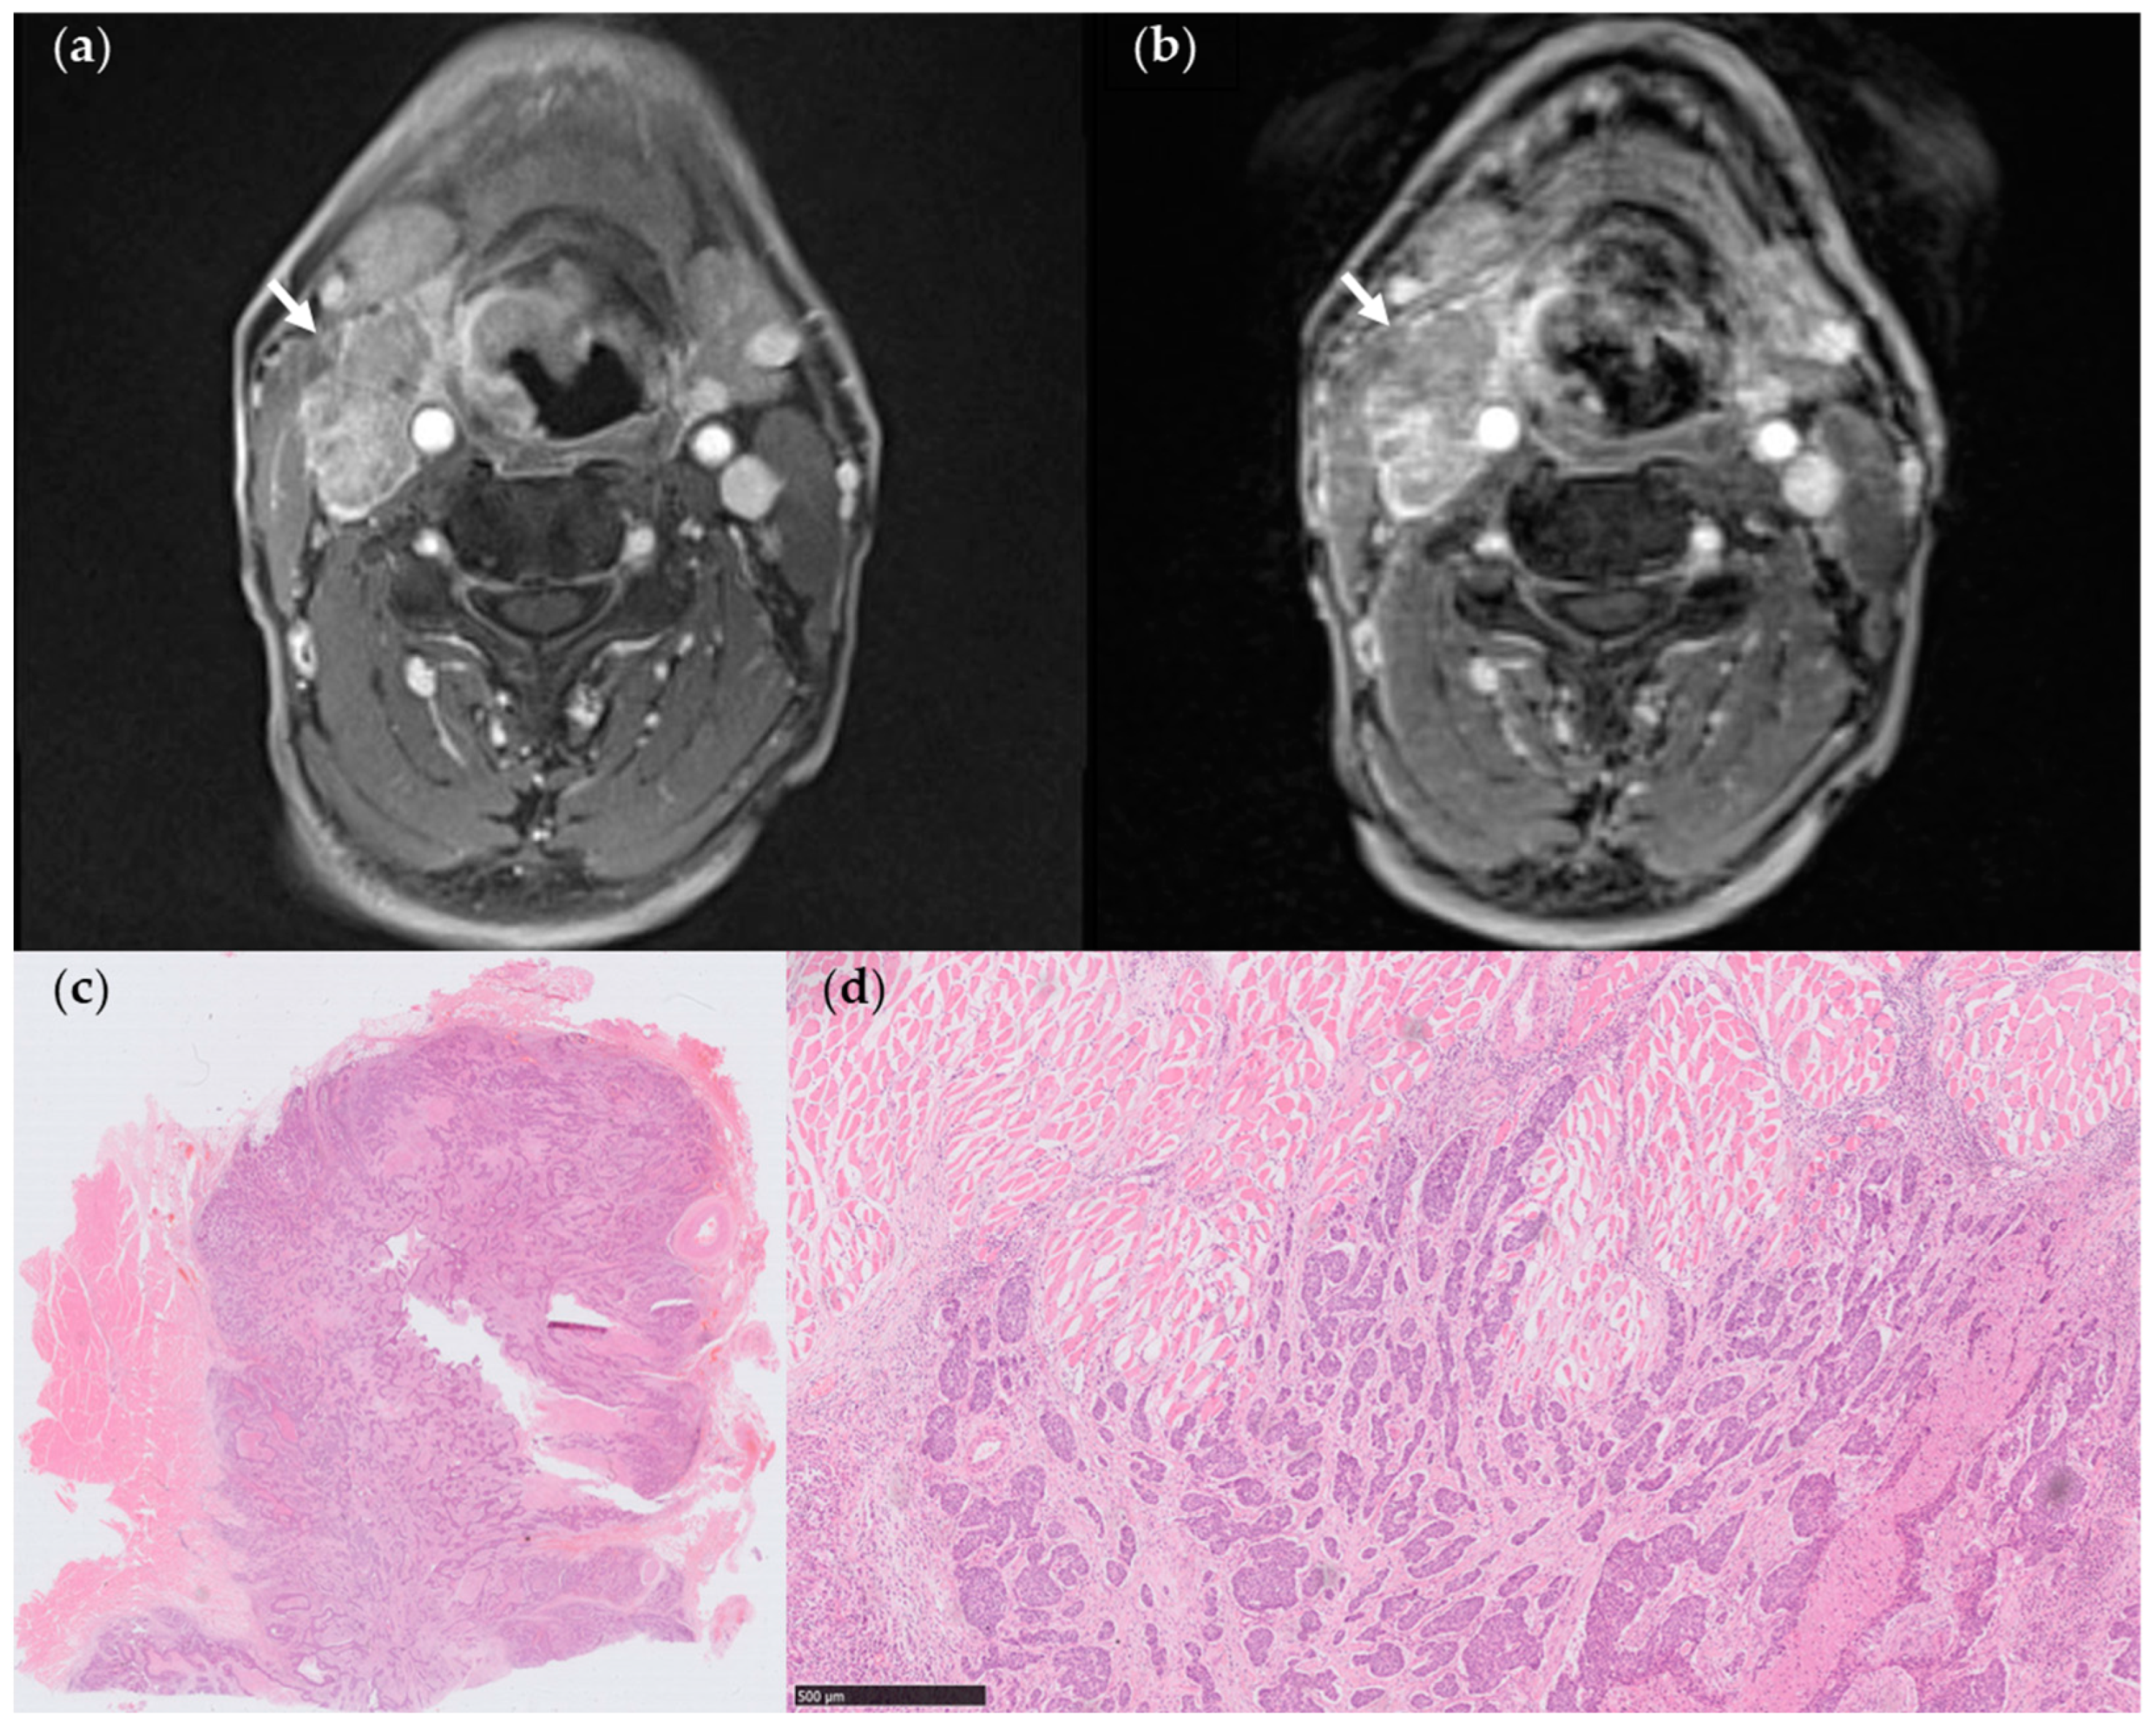

3.3. Association of MR Features with Histologically Confirmed ENE

4. Discussion